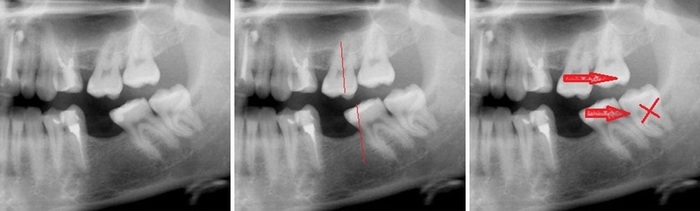

Ниже, правда, представлен пример не с 8ым зубом, но смысл тот же. При отсутствии любого зуба, его антагонист (тот зуб, с которым он смыкается) начинает постепенно выдвигаться в сторону отсутствующего «пытаясь» найти себе контакт.

Поставить имплантат в область 7-ого зуба не проблема, но спротезировать (установить коронку) такой зуб правильно будет невозможно. Почему? Потому что коронка в таком случае будет в два раза ниже по высоте. И образуется так называемый «блок», при движении нижней челюсти, о котором я упоминал в этой статье.